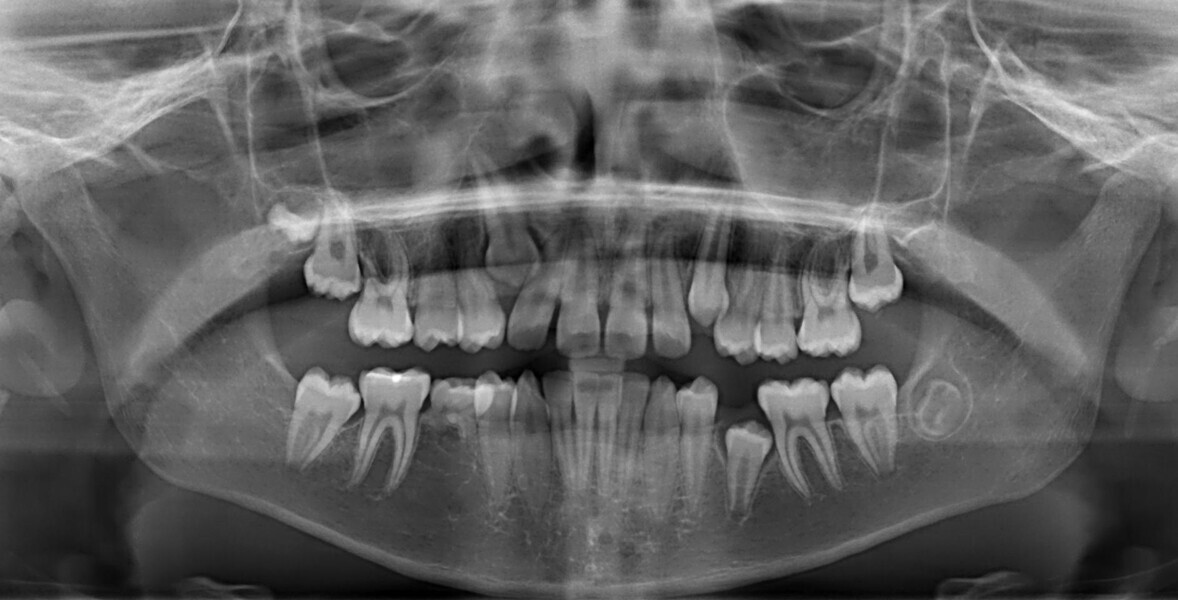

A 14-year-old female patient presented with the chief complaint of midline deviation and dental crowding in both arches. Facial analysis showed a hypodivergent growth pattern, a normal nasolabial angle, a harmonious profile and proper chin projection. Clinical examination revealed a Class III skeletal relationship (ANB = 0°) and Class I molar relationship. The maxillary right canine was absent, and this had led to space loss and mesial drift of posterior teeth on the right side, resulting in a slight Class II molar relationship. The maxillary left canine had erupted in a high position. The mandibular arch displayed crowding despite the agenesis of the right second premolar and the persistence of the primary molar (Figs. 3–11). The radiograph showed the probably premature loss of the maxillary right primary canine and consequently impacted maxillary right permanent canine, and the agenesis of the mandibular right second premolar and the mandibular right third molar (Fig. 12).

Fig. 3